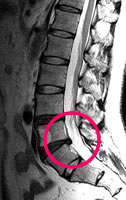

腰椎MRI

腰椎椎間板ヘルニア

最近、坐骨神経痛が出現し、詳しい検査を希望。

腰痛、お尻から足にかけてのしびれ、痛みのある方にお勧めします。

| 腰椎MRI | 14,300円 | 腰の痛み 足のしびれや痛み ぎっくり腰など | 腰椎椎間板ヘルニア 腰部脊柱管狭窄症 |